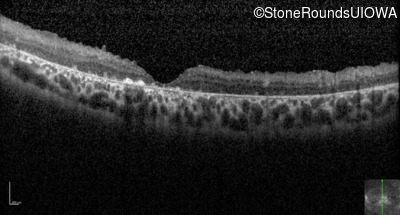

Optical Coherence Tomography - Left - 20/250 sc

Exemplar / OCT Stack